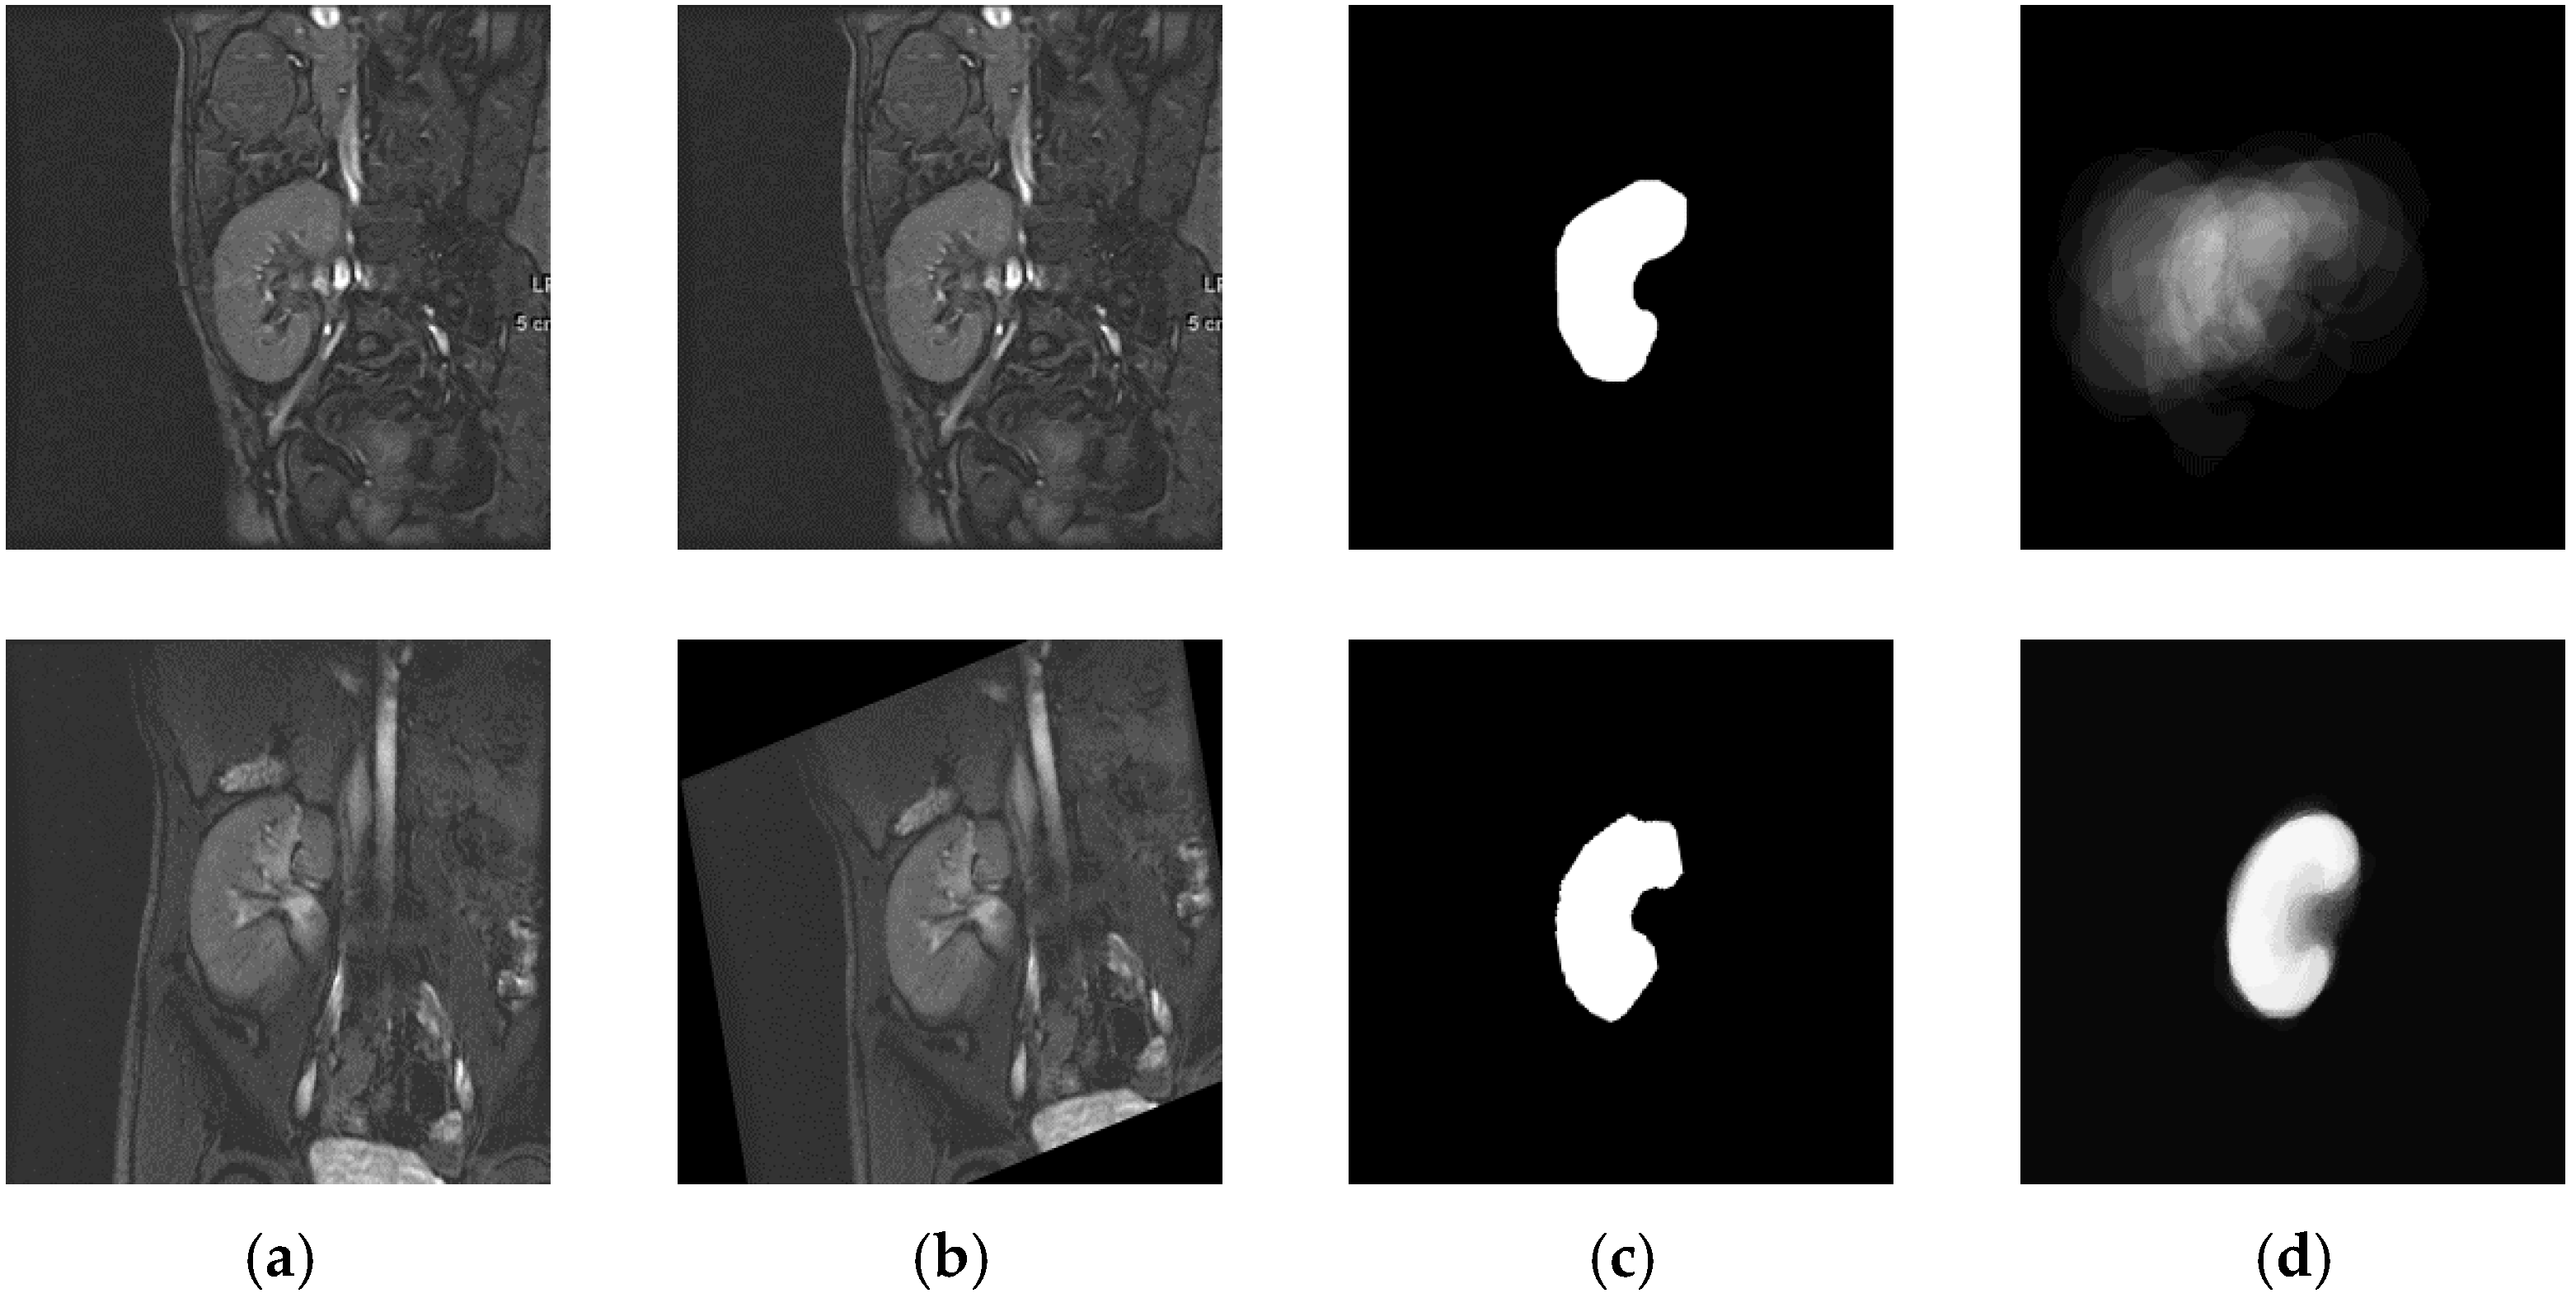

2.1. Materials

2.5. Statistical Kidney Shape Model